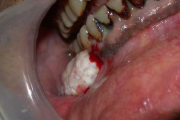

Mehaaniline trauma

pidev põse närimine